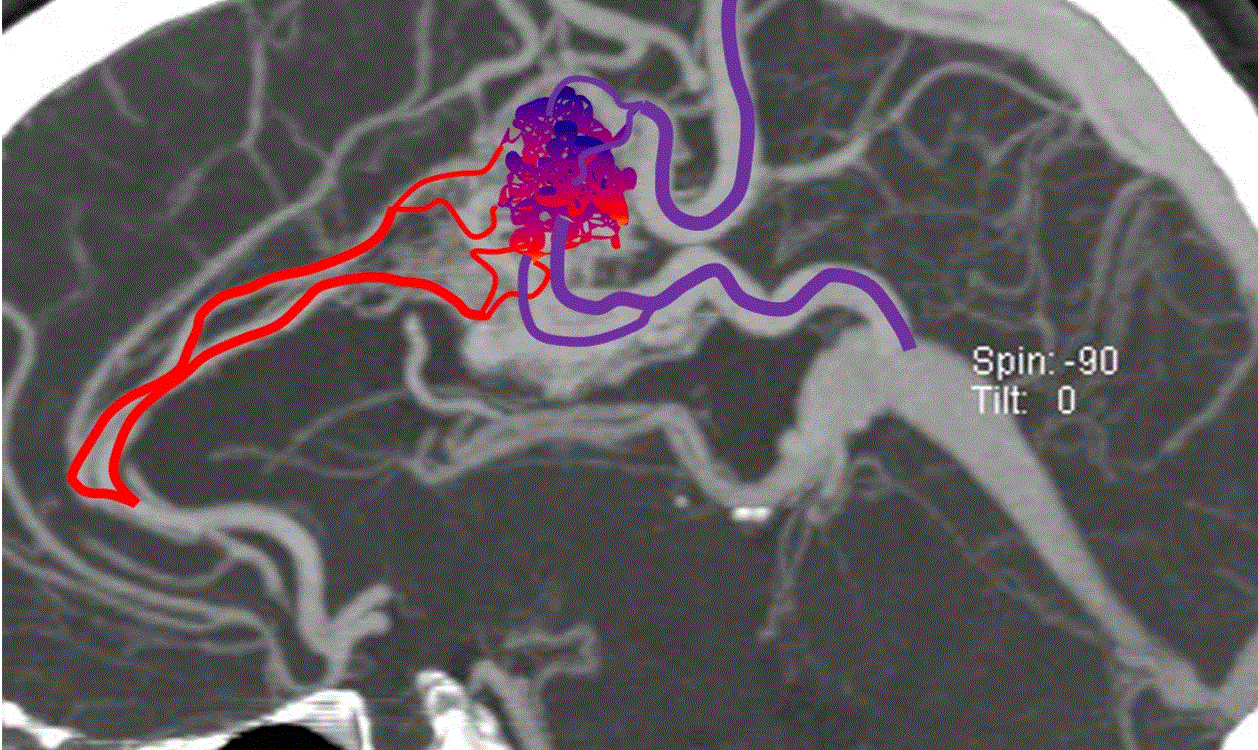

It is not clear why AVM’s form, but some researchers believe that these tangles of vessels are present from birth (a congenital disorder). Several rare genetic diseases are associated with AVM’s. AVM’s classically appear as a complex tangle of abnormal thinly-walled vessels called a “nidus”. A distinguishing feature is that they occur anywhere within the brain or spinal cord. AVM’s are rare, occurring in about 0.2% of the population (200 cases per 100,000 people).

While a CT (computed tomography) or MRI (magnetic resonance imaging) test of either the brain or spinal cord will typically first detect these lesions, catheter-based diagnostic (cerebral or spinal) angiography is essential to fully understand and characterize the AVM. This evaluation allows your doctor to determine your future risk of symptoms and your treatment options. Treatment of an AVM depends on whether symptoms are present or not, how large the lesion is, where it is located and a host of other features only determined by the diagnostic (cerebral or spinal) angiogram.